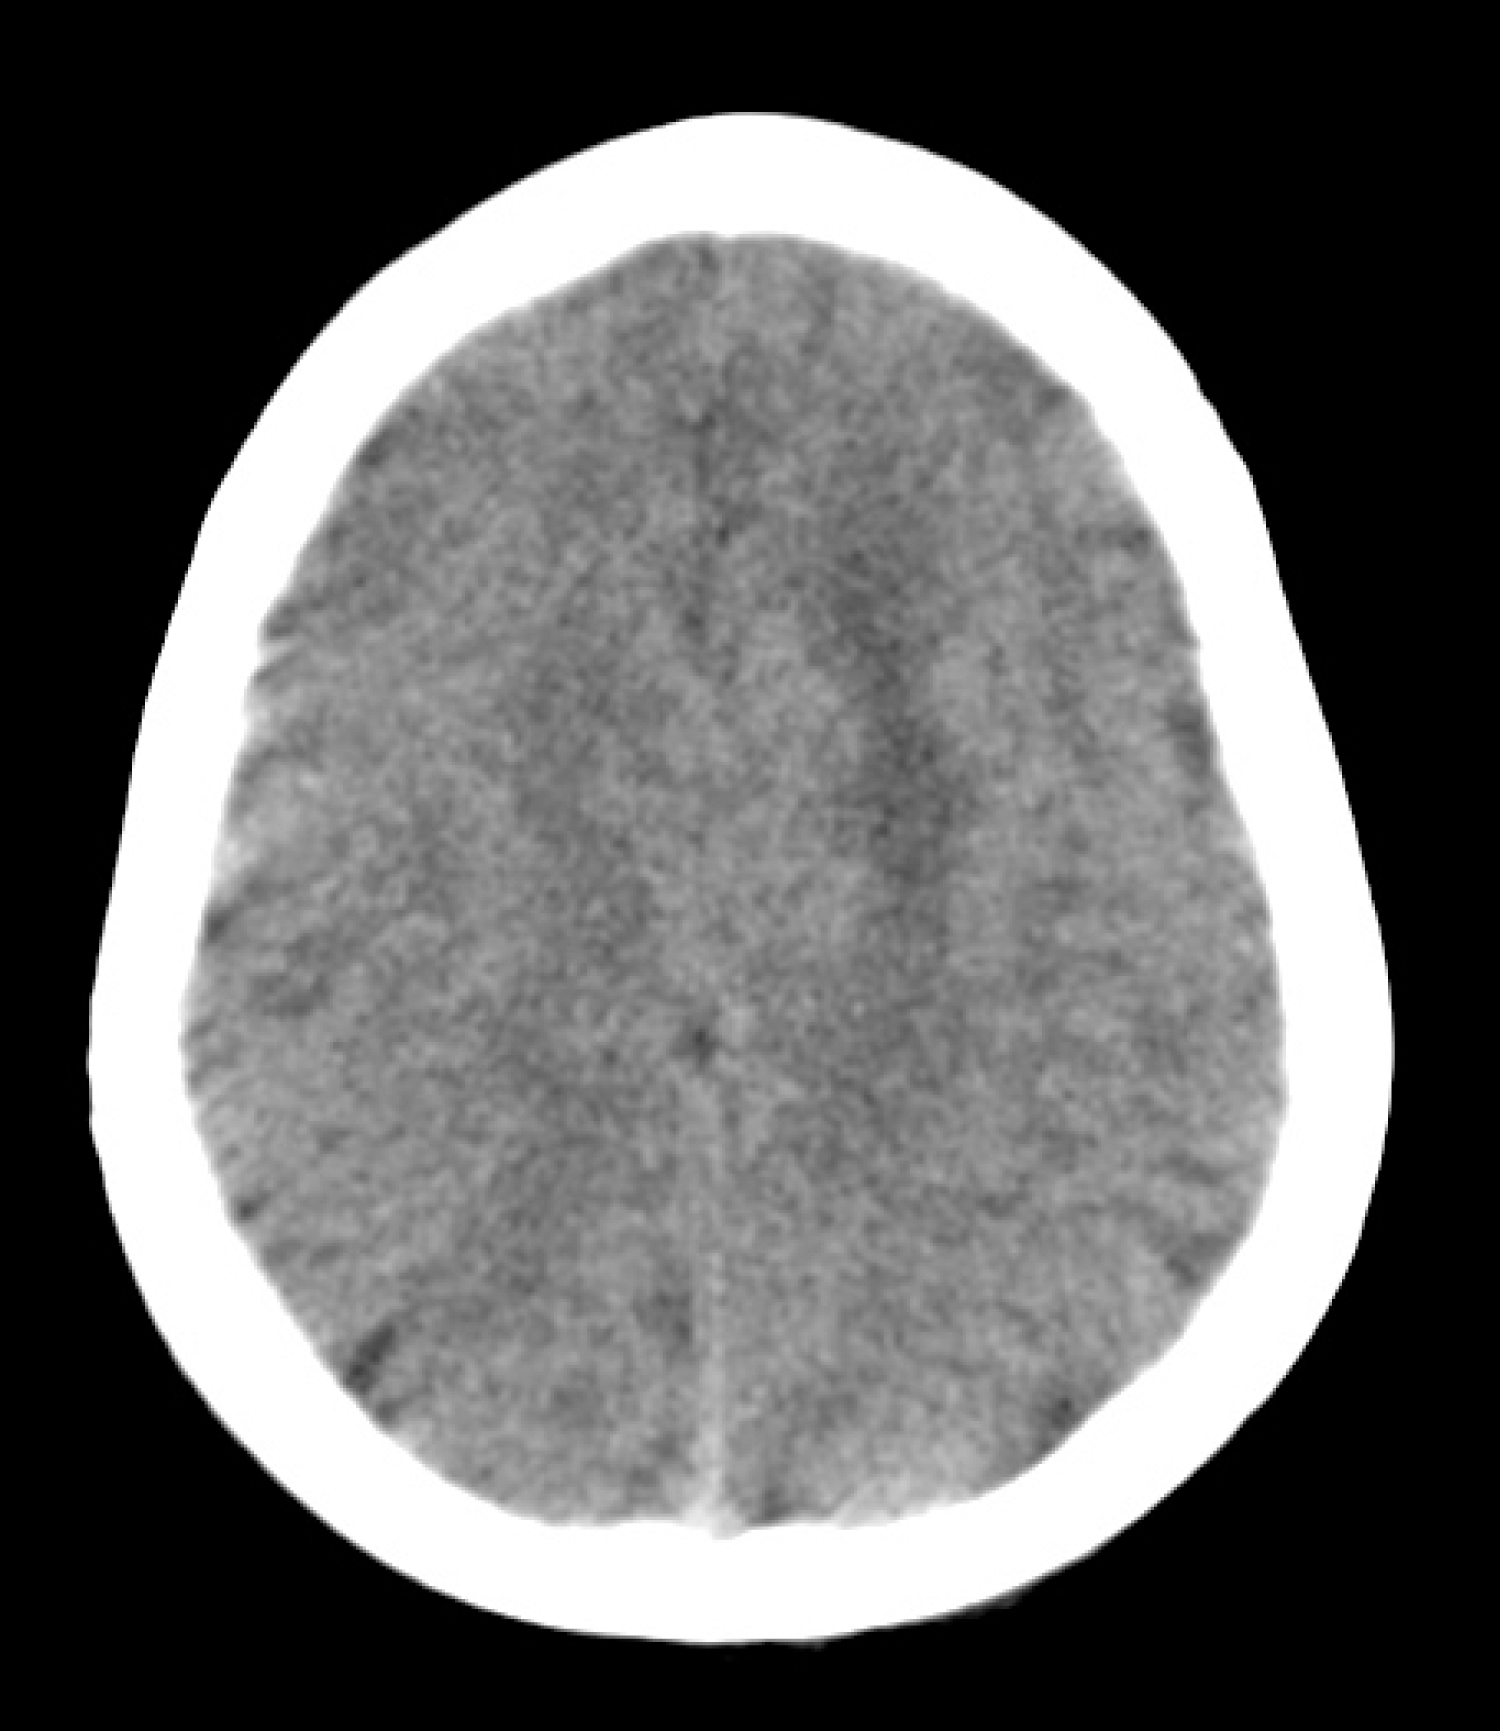

Brain CT scan revealed a poorly demarcated hypodense zone in the left frontal lobe (Figure 1). MRI showed a 1.6 × 1.5 × 1.5 cm, homogeneously enhanced lesion within the subcortical region of the left superior frontal gyrus with compression of the cingulate gyrus and supplementary motor cortex (Figure 2a and Figure 2b). The spectroscopy shoed an altered choline/creatinine ratio and decreased NAA, suggestive of a glial tumor (Figure 2c).

Figure 1: Non-contrasted brain CT scan. Axial cut showing a poorly demarcated hypodense zone in the left frontal lobe.

CT = Computed Tomography. View Figure 1

The patient was diagnosed 2 years earlier with idiopathic complex focal epilepsy, with partial control of the convulsive activity with Levetiracetam 1 gr/day and Magnesium Valproate 1.2 gr/day; parents reported two to three seizures per week with the characteristics already described before admission. CT scans of the brain performed as part of the diagnosis approach were considered normal (Figure 1) shows the CT scan performed before neurosurgical evaluation). Moreover, multiple EEGs, of which only its general characteristics could be documented, reported abnormal spike-and-slow-wave complexes in paroxysms of up to 10 seconds, without identification of a specific epileptogenic location.